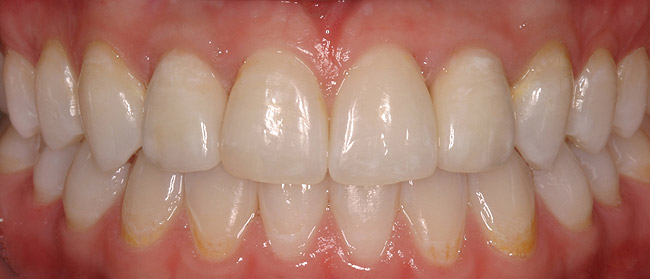

Figure 7c  Completed single all-ceramic screw-retained implant crown site on tooth No. 9, revised porcelain three-quarter laminate veneers for teeth Nos. 8 and 9, cemented with Kerr NX3 Nexus¬Æ Third Generation Dual Cure Resin cement.

Figure 7c

Figure 7d  Completed single all-ceramic screw-retained implant crown site on tooth No. 9, revised porcelain three-quarter laminate veneers for teeth Nos. 8 and 9, cemented with Kerr NX3 Nexus¬Æ Third Generation Dual Cure Resin cement.

Figure 7d

Figure 7e  Completed single all-ceramic screw-retained implant crown site on tooth No. 9, revised porcelain three-quarter laminate veneers for teeth Nos. 8 and 9, cemented with Kerr NX3 Nexus¬Æ Third Generation Dual Cure Resin cement.

Figure 7e